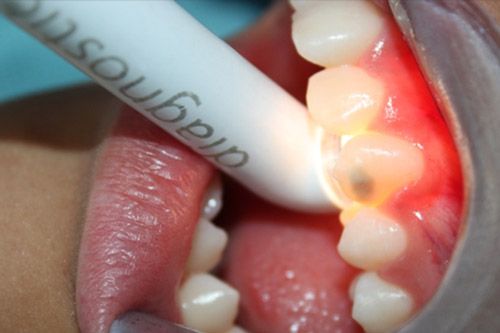

Se utilizó una lámpara para transiluminación Radii plus de SDI, la cual cuenta con una punta de diagnóstico con un led blanco que da dos intensidades, se observa que la luz no atraviesa la zona afectada, (esto quiere decir que la lesión es muy profunda y no podrá ser infiltrada con icon, por lo que se decide arenar o utilizar microabrasión).